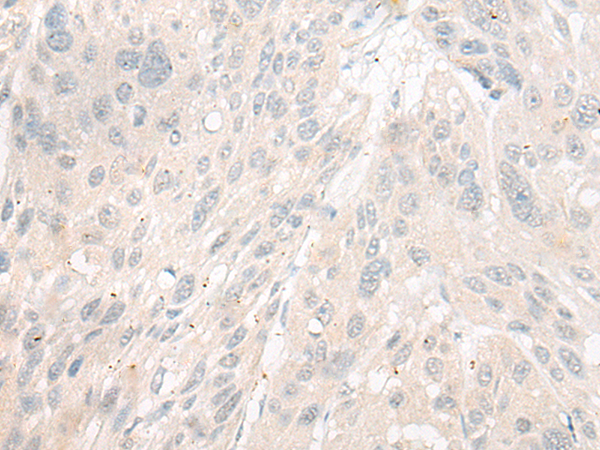

ELISA, IHC |

IHC positive control: |

Human thyroid cancer and Human esophagus cancer |

IHC Recommend dilution: |

25-100 |